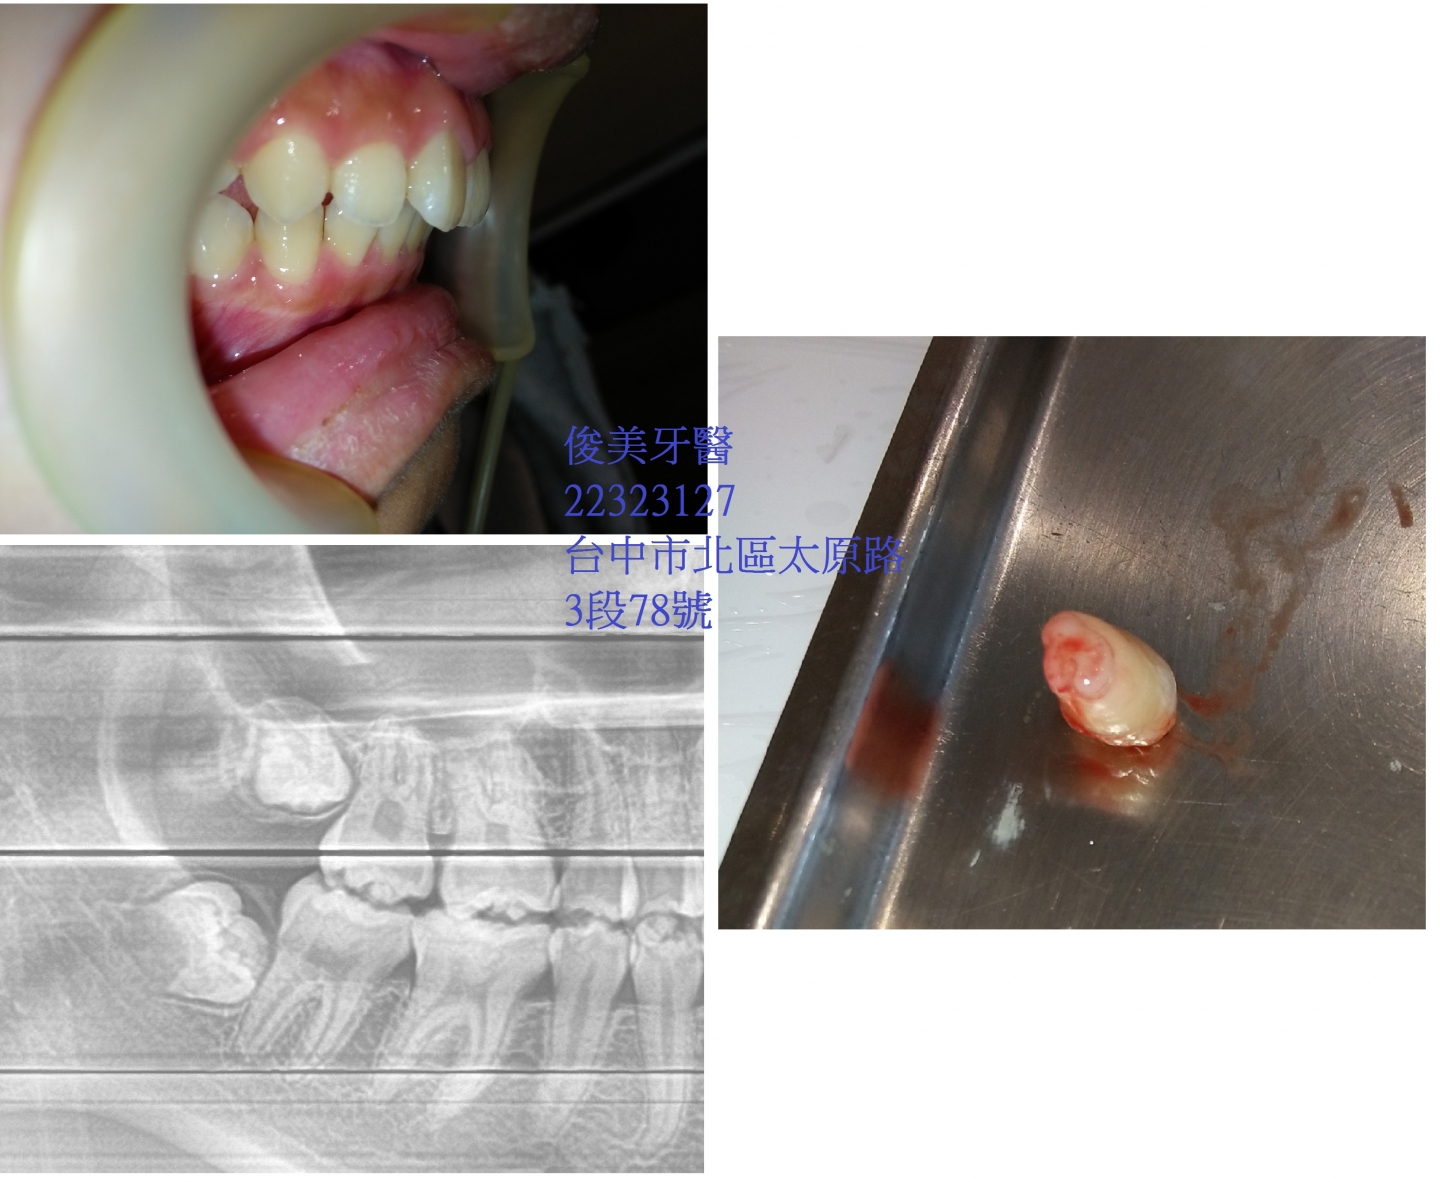

埋伏智齒拔除案例11

患者因牙齒已太前凸, 來就診,經x 光檢查,發現有埋伏智齒,醫師建議需拔除,以免

造成牙齒前凸更加嚴重,再配合其他療程來做治療。

拔出後需冰敷3 天,減輕腫脹,一週後回診拆線即可。

目前恢復良好 。